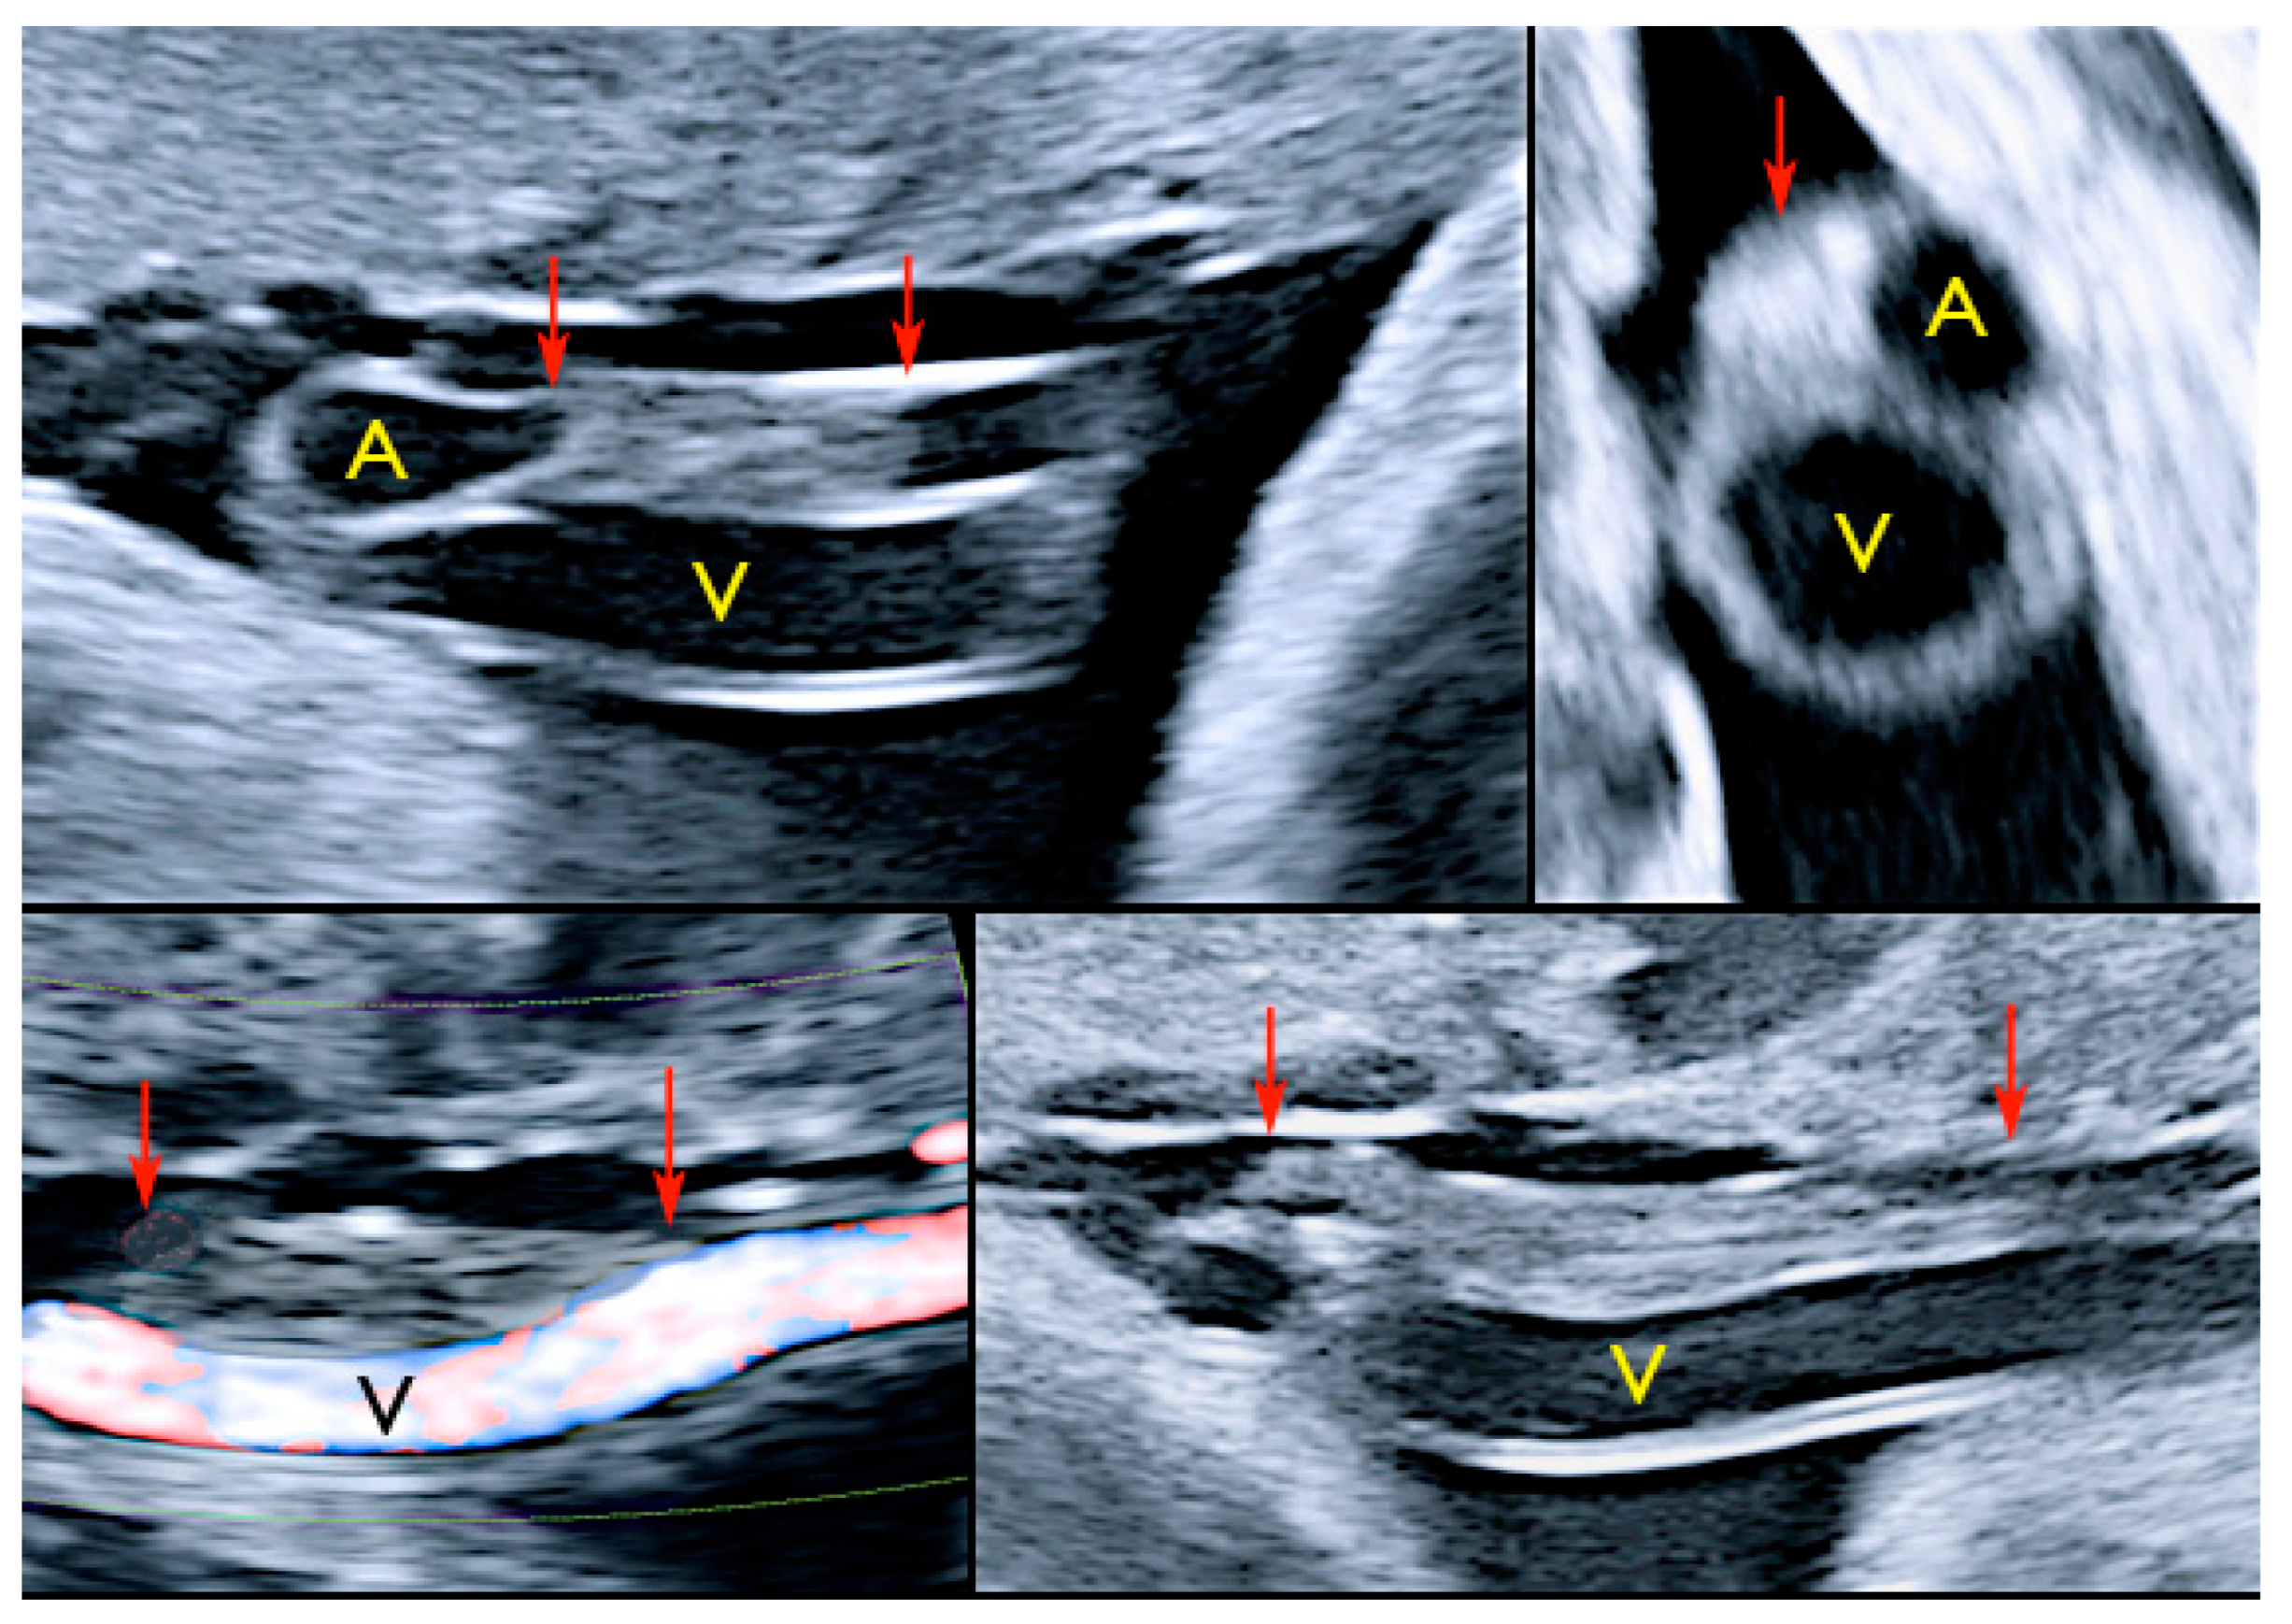

3.2.2. Vasa Praevia

3.2.3. Velamentous Umbilical Cord Insertion